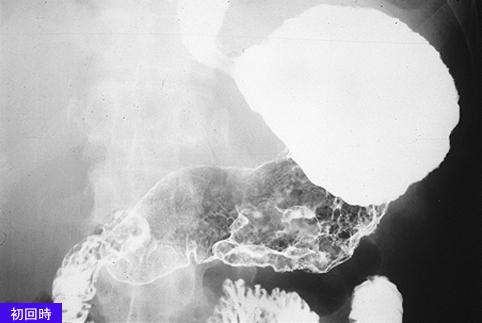

A case of type 4 advanced gastric cancers with multiple metastases to the esophagus.

Tokyo Pref., Cooperative study between National Cancer Center and Kyushu Cancer Center

1980-1984's case

Malignant epithelial tumor/Adenocarcinoma

Stomach/More than one of above

X-ray

Type 4 Diffusely infiltrating type/

40 -